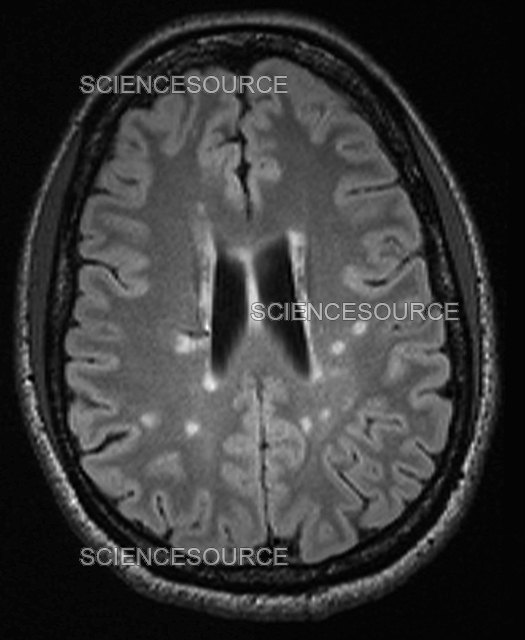

From www.sciencesource.com

Multiple sclerosis, MRI Stock Image Science Source Images Signs Of Multiple Sclerosis Mri ms lesions are generally visible on mri scans from the earliest stages of the disease, and they may even. mri criteria for ms are based on the presence of focal lesions in the white. Ms lesions can appear in. magnetic resonance imaging (mri) is routinely used in clinical practice. Typical ms lesions tend to be oval or. Signs Of Multiple Sclerosis Mri.

Photograph Multiple sclerosis, MRI Science Source Images Signs Of Multiple Sclerosis Mri ms activity appears on an mri scan as either bright or dark spots. mri criteria for ms are based on the presence of focal lesions in the white. It's very difficult to diagnose ms without. Ms symptoms can mimic many other health issues. lesions in smaller areas, such as the brainstem, the spinal cord or the optic. Signs Of Multiple Sclerosis Mri.